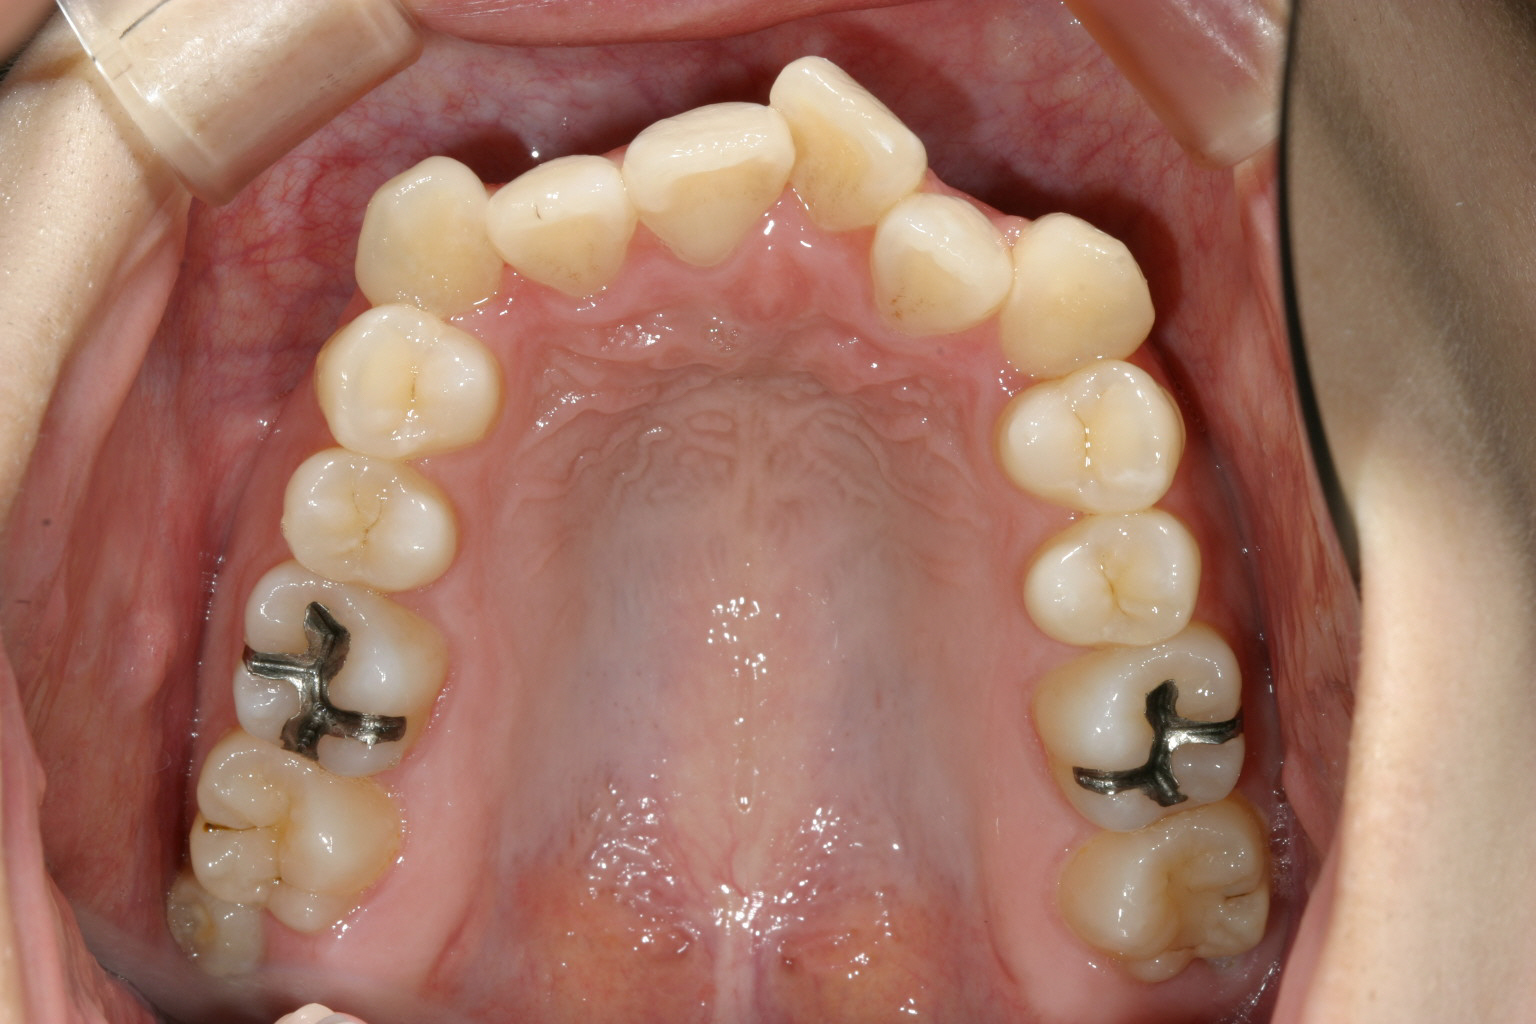

アーチが狭い為に前歯が並ばずガタガタになっています。

アーチをU字に広げ多少のIPR(隙間削合)を行っています。